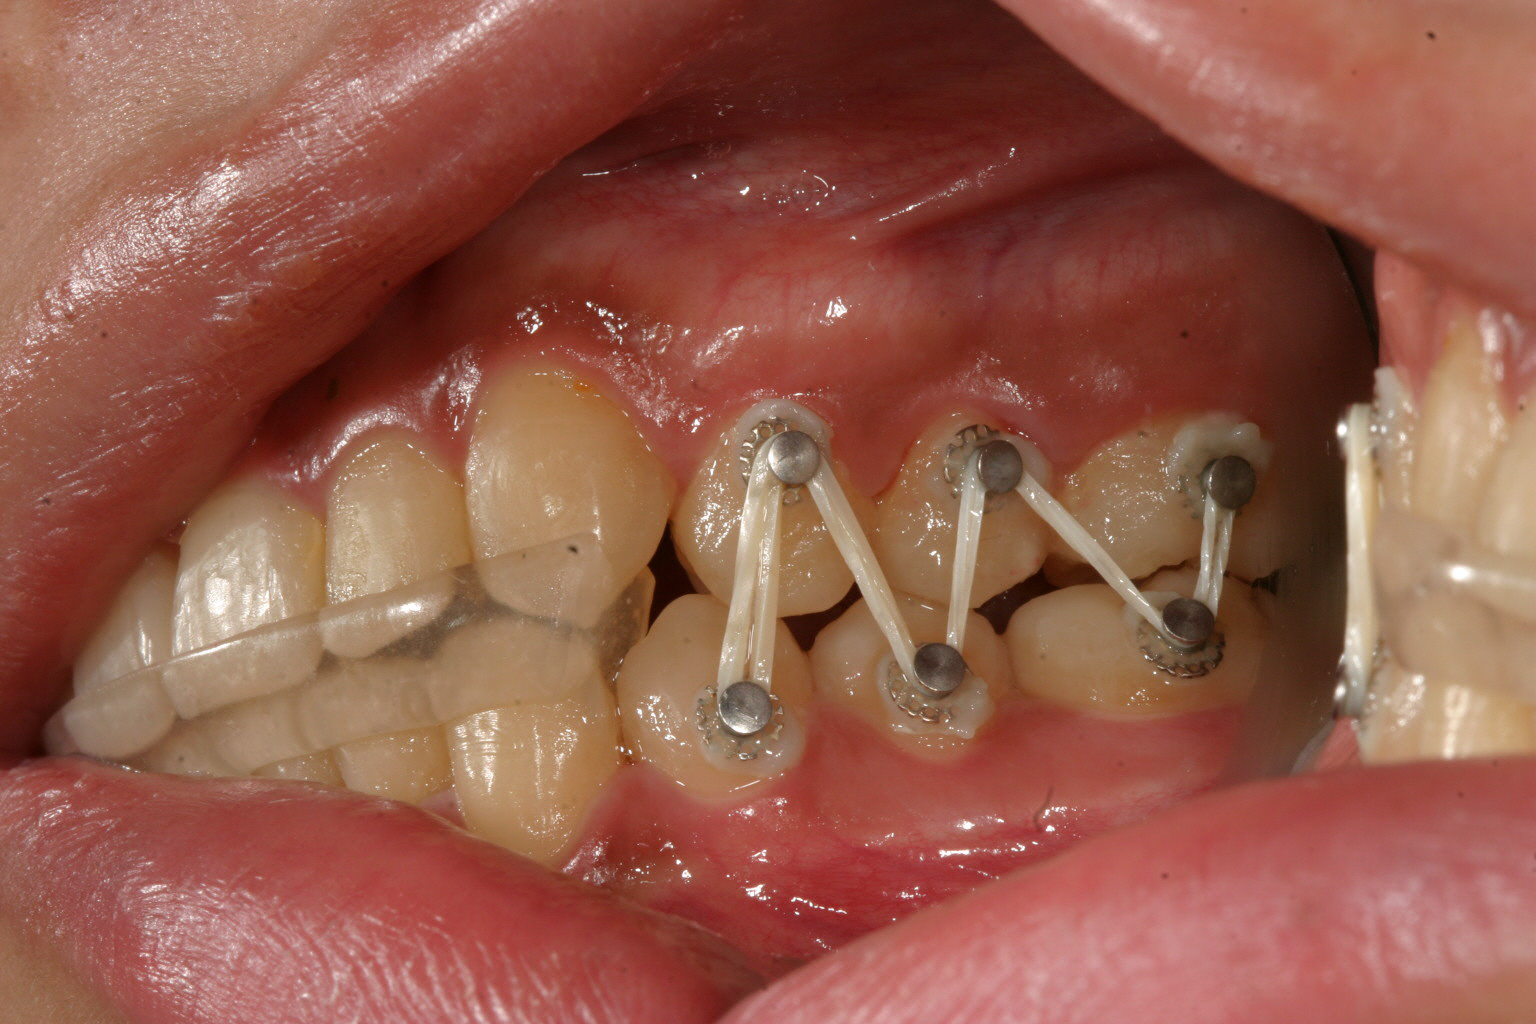

左側のアップダウンエラスティックです。